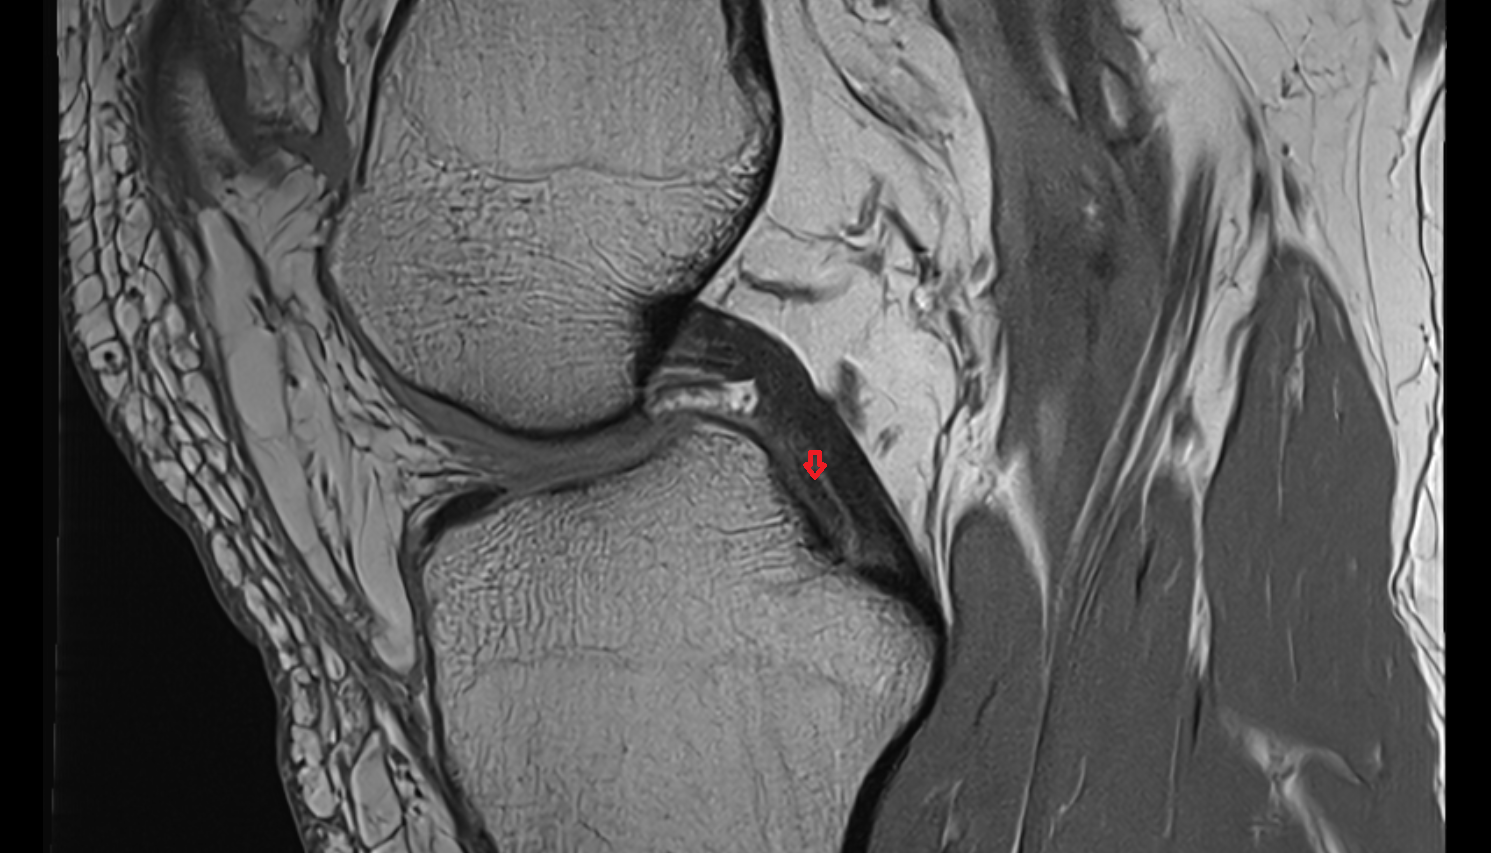

- Anterior cruciate ligament

- Posterior cruciate ligament

- Infrapatellar fat pad